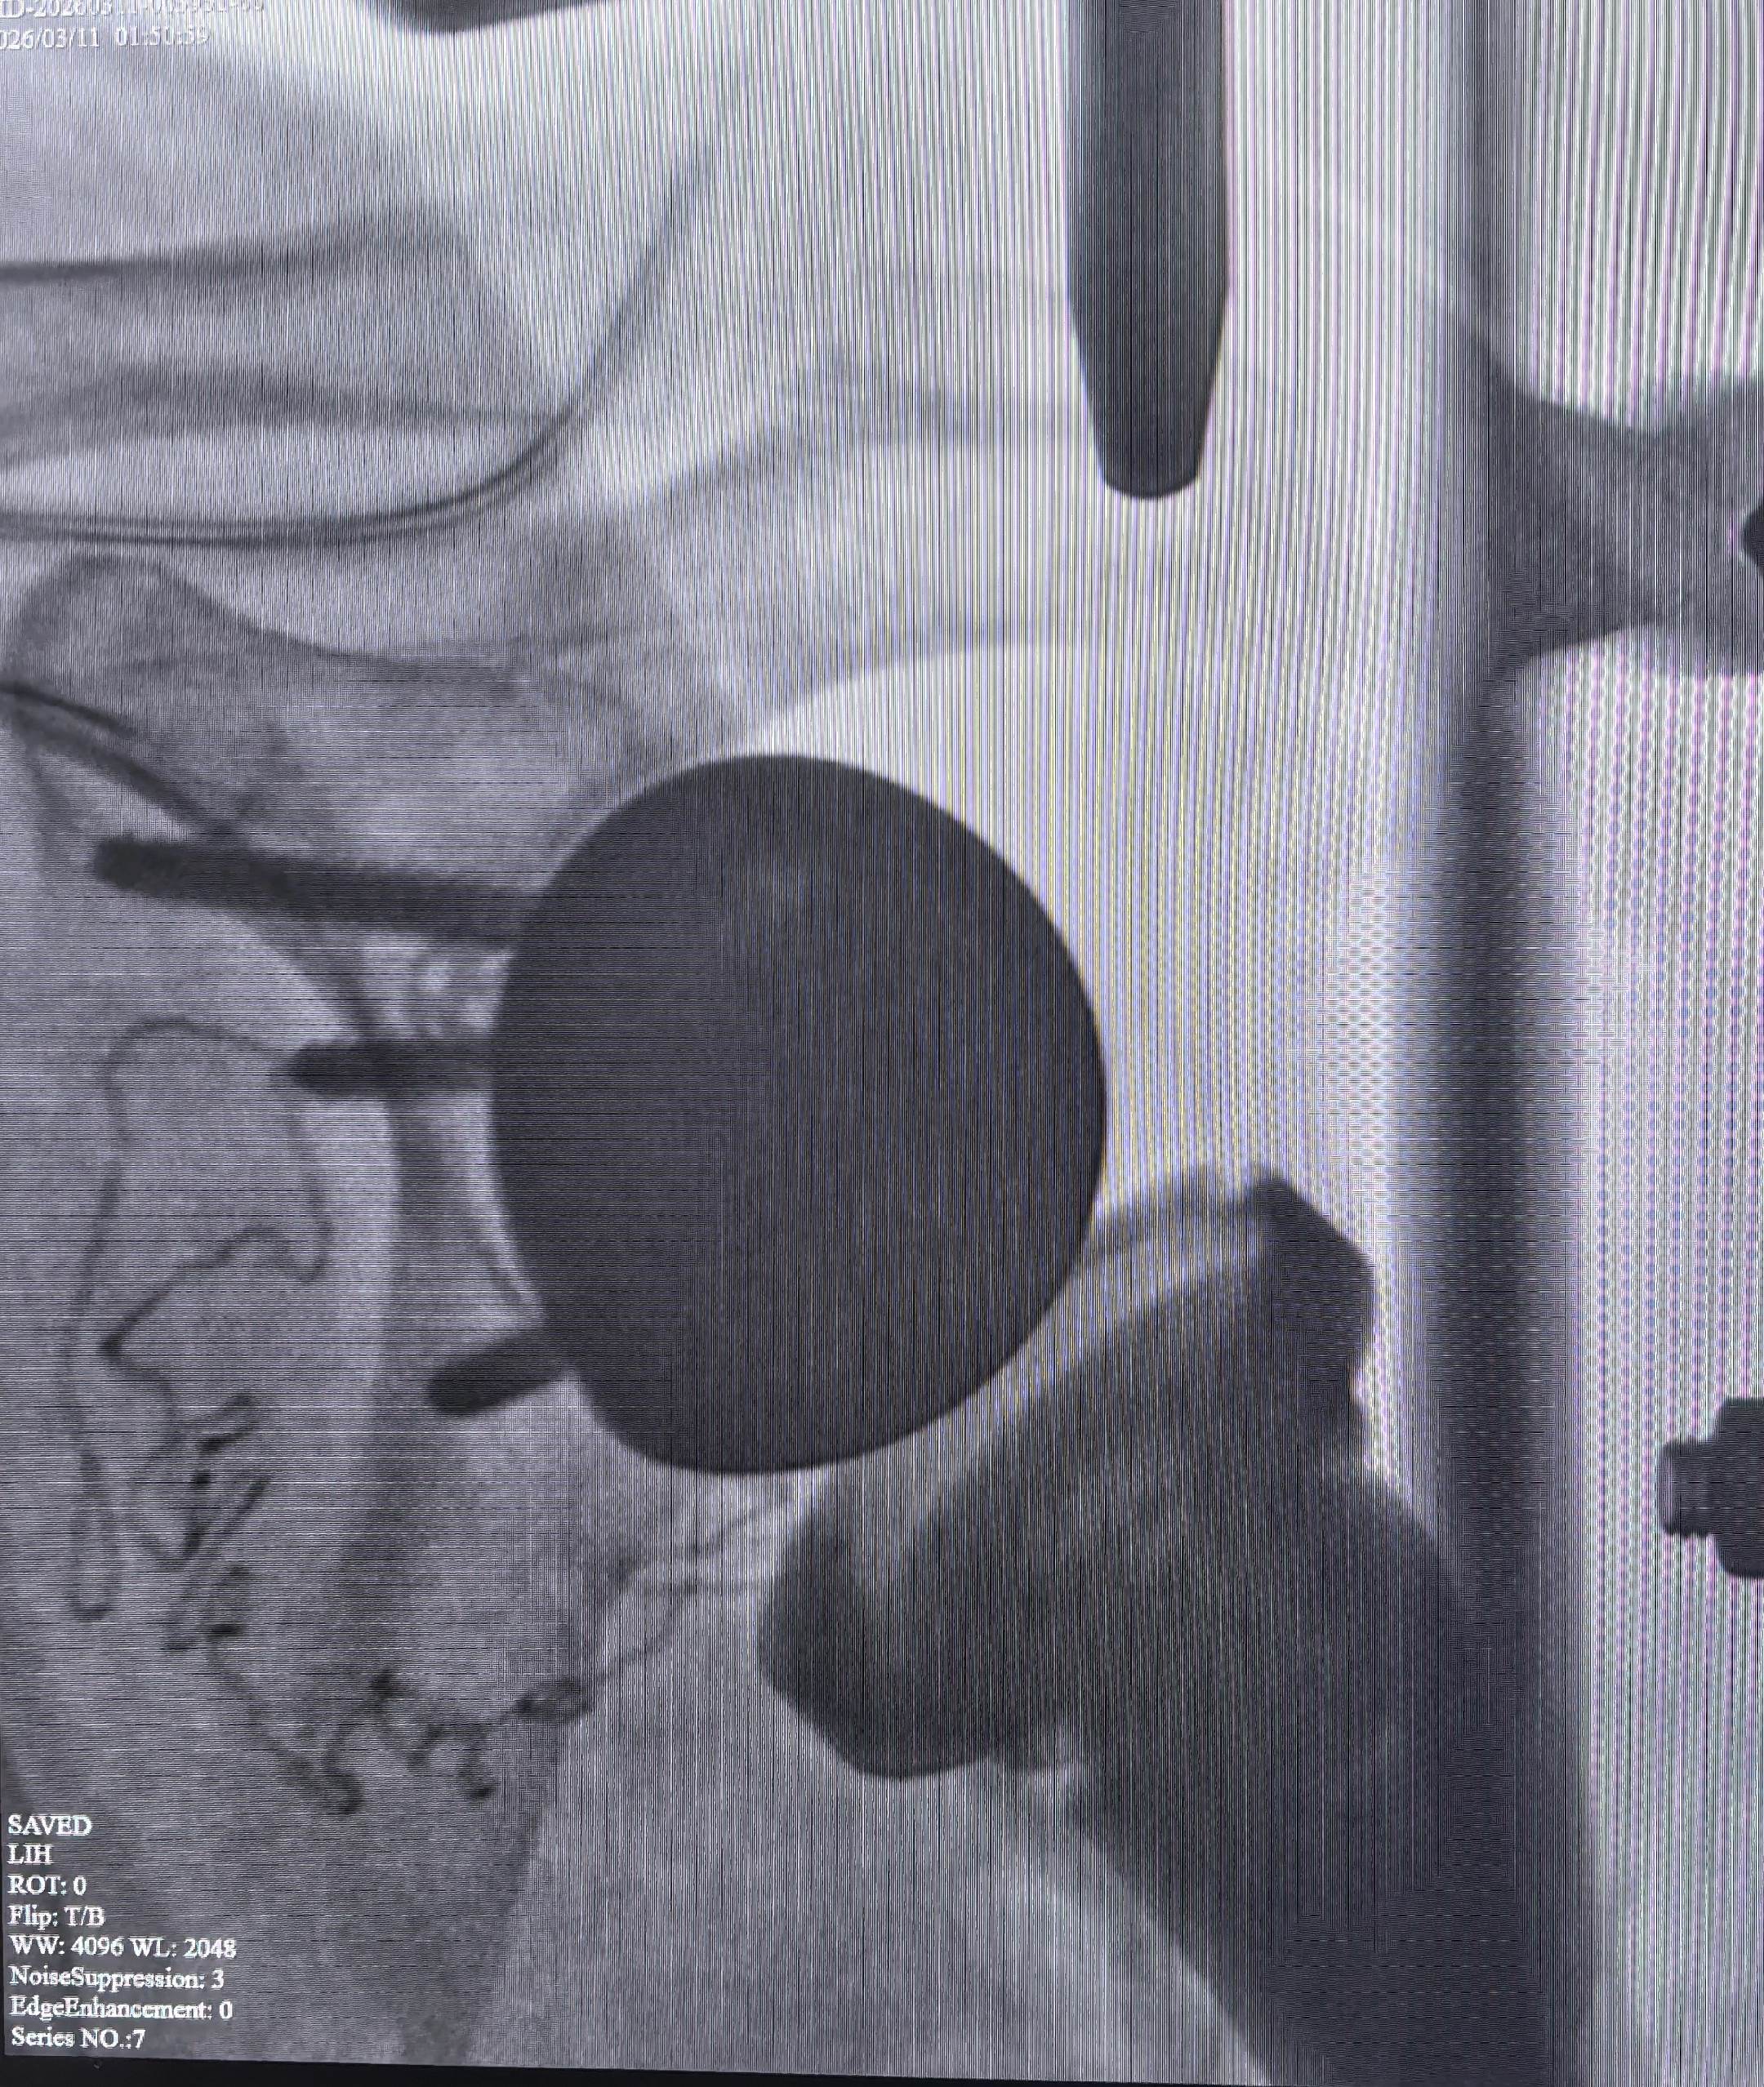

反肩关节置换。陈旧性肱骨近端粉碎骨折,RTSA完美解决。